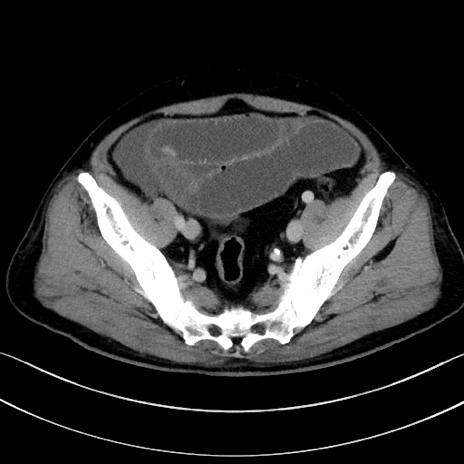

症例15(横断像)

【症例】70歳代男性

【主訴】腹痛

【現病歴】今朝から腹痛あり。全体的に痛い。特に左上の方。排ガスが今日はない。冷や汗が出る。

【既往歴】直腸癌術後

【身体所見】左側腹部〜上腹部に圧痛あり。腹膜刺激症状明らかなではない。軽度反跳痛。左下腹部に術後瘢痕あり。

【データ】WBC 7700、CRP 0.02